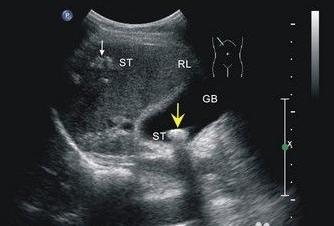

★B超检查

对膀胱充盈的猫可直接进行B超检査,正常的膀胱超声图像呈1个无回声的液性暗区,若有结石,图像上会出现较明亮的强回声光点或团块,伴有明显的声影。结石会随着动物体位的变化而变化,小的结石或结晶等会在膀胱中上下沉浮,通过改变动物的体位,观察强光点随着体位改变的变化,借此方法可以排除肿瘤等其他原因引起的强回声反射。炎症情况下或结石长期刺激,有时可见增厚的膀胱壁。